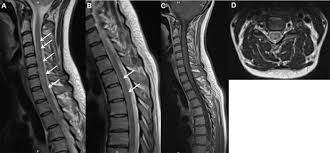

Partial transverse myelitis and partial myelitis are terms sometimes used to specify inflammation that only affects part of the width of the spinal cord. Other conditions often discussed in this group due to similar imaging include: Ischemia as a result of arterial infarction is typically located in the anterior parts, but may involve the entire transverse diameter. Tm is characterized by weakness and numbness of the limbs. Axial t2 (bottom row right) also demonstrates hyperintense edema within the central cord.

Transverse myelitis is associated with viral infections, vaccinations, autoimmune processes, and cancer, although most cases are idiopathic. When complete, both the anterior and posterior regions of the cord are involved; Ischemia as a result of arterial infarction is typically located in the anterior parts, but may involve the entire transverse diameter. Acute transverse myelitis is an inflammatory disorder of the spinal cord in which there is no evidence of spinal cord compression. Axial t2 (bottom row right) also demonstrates hyperintense edema within the central cord.

Ms typically is triangular in shape and mostly located dorsally or laterally. Ischemia as a result of arterial infarction is typically located in the anterior parts, but may involve the entire transverse diameter. Lee jw (1), park ks, kim jh, choi jy, hong sh, park sh, kang hs. Axial t2 (bottom row right) also demonstrates hyperintense edema within the central cord. Further criteria divide transverse myelitis into two main groups. Myelitis, is a collective term simply referring to any inflammation of the spinal cord. A case of transverse myelitis following catheterization of the right fifth intercostal artery is reported here to emphasize the fact that bronchial arteriography does carry some hazard which must be assessed in the light of the presenting clinical problem. Viral, neurosyphilis 2 , autoimmune, post vaccination etc.